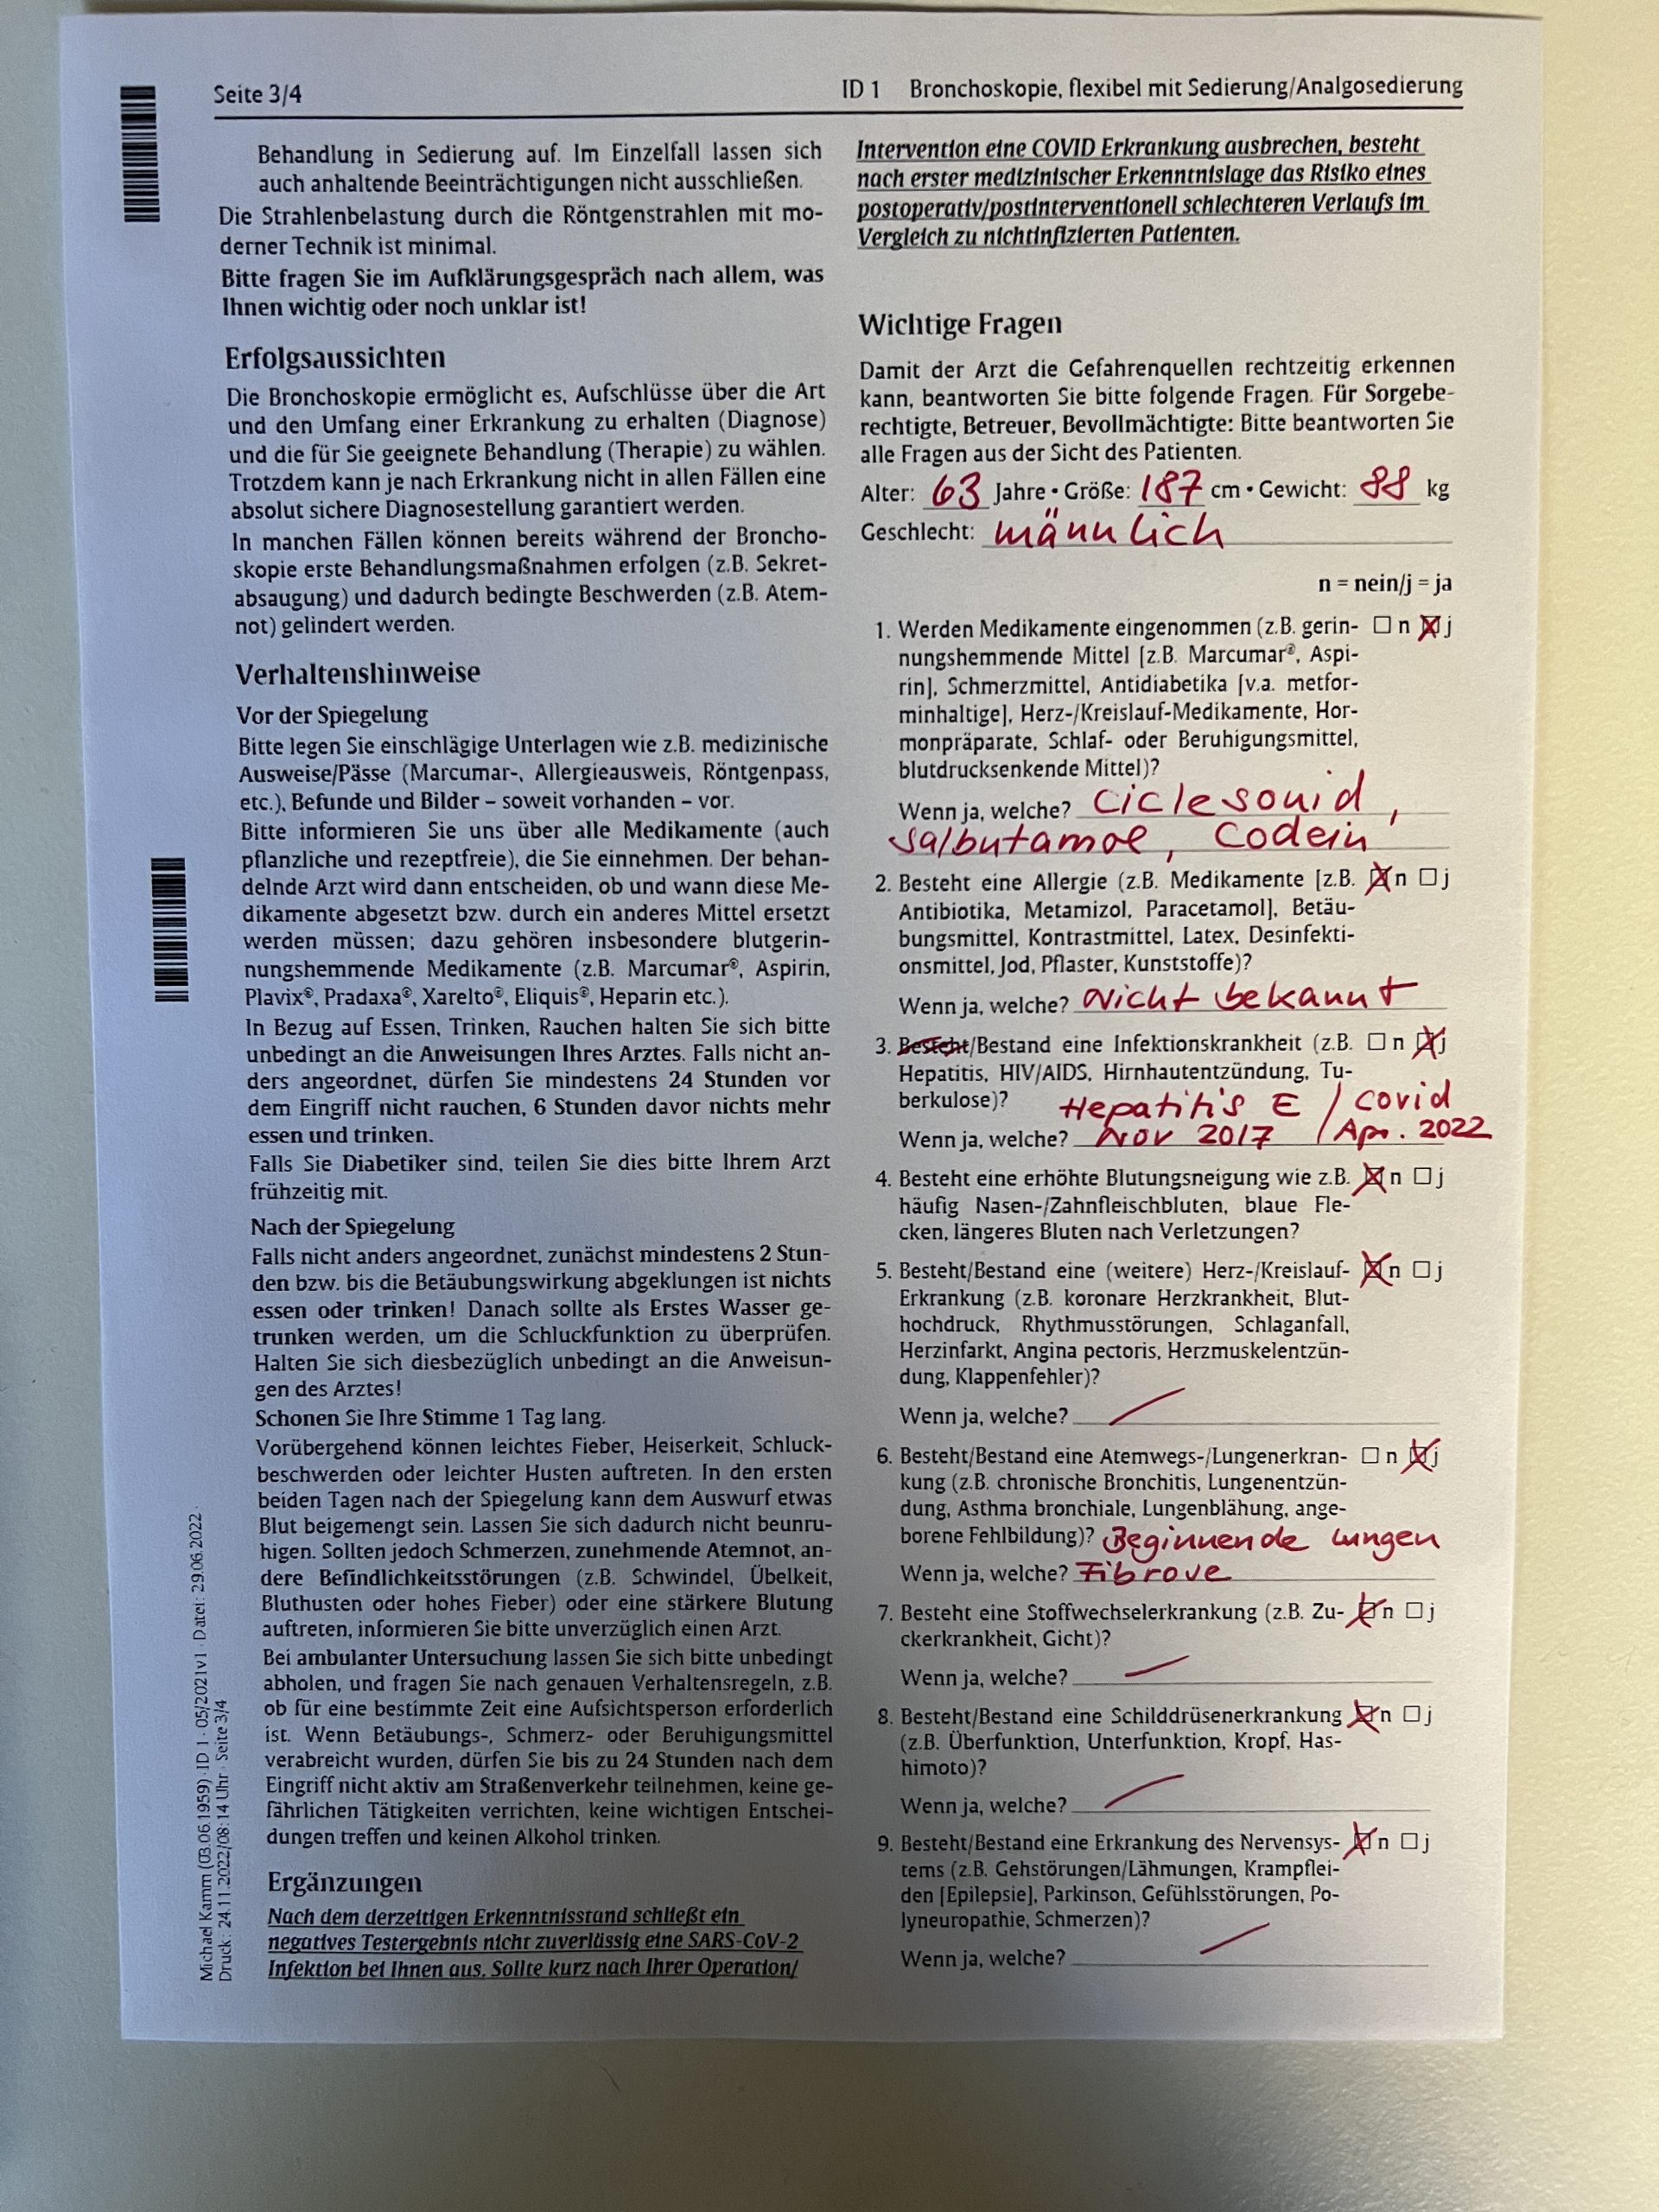

Eine leider festgestellte fortschreitende Veränderung meines Lungengerüsts durch eine Fibrose bedurfte Ende November einer exakten Diagnose der genauen Erkrankungsursache. Hierzu war eine Bronchioskopie mit Gewebeentnahme im Rahmen eines stationären Aufenthalts in einer Klinik notwendig. Erst auf Basis einer belastbaren Diagnostik ist die optimale Entscheidung eines Pneumologen bezüglich der Bestimmung einer passenden Therapie möglich. Nicht schön, aber unumgänglich. Ich entscheide mich aus rein praktikablen Gründen für das Bogenhausener Klinikum, da dieses städtische Krankenhaus nahe zu uns liegt und zudem über eine Lungenabteilung mit gutem Ruf verfügt. Die Lungenbiopsie zählt zu den diagnostischen Verfahren der Medizin. Sie hat vor allem im Bereich der Lungenheilkunde zur Gewinnung von Lungengewebe einen großen Stellenwert. Das mittels Lungenbiopsie gewonnene Gewebe kann einer Vielzahl an weiteren Untersuchungen unterzogen werden, beispielsweise histologischen, zytologischen, immunologischen oder genetischen Tests. Die Lungenbiopsie gehört zu den invasiven Verfahren der Diagnostik. Sie kommt daher nur äußerst selten als erstes diagnostisches Verfahren zum Einsatz. Prinzipiell sollte jede Erkrankung des Lungengewebes, die sich durch klinische Symptome bemerkbar macht und mittels radiologischen Verfahren nachweisbar ist, mittels einer Lungenbiopsie weiter klassifiziert werden müssen. Erkrankungen des Lungengewebes umfassen dabei Veränderungen im Bereich der Lungengefäße, des Lungengewebes – dem Parenchym – selbst oder der Pleura. Biopsien im Inneren eines Lungenlappens sind im Rahmen einer Bronchoskopie entnehmbar: Nach Einführung des Bronchoskops über den Rachen und den Hals in den zu untersuchenden Lungenflügel wird das zu biopsierende Areal aufgesucht. Mittels einer Biopsiezange - in meinem Fall war es eine vereiste Metallspitze - wird ein Stück des Lungengewebes gefasst, herausgetrennt und durch das Bronchoskop herausgezogen. Als Komplikation kann eine Blutung des biopsierten Lungengewebes auftreten. Dieses Verfahren hat von den oben genannten die geringste Invasivität, da keine Körperhöhlen eröffnet werden. Es kann auch bei gesundheitlich schwer angeschlagenen Patienten verwendet werden. Biopsien mittels Thorakoskopie müssen im Operationssaal unter sterilen Bedingungen durchgeführt werden. In Lokalanästhesie wird durch einen kleinen Schnitt ein Thorakoskop in die Brusthöhle eingeführt und mit einer Biopsiezange Lungengewebe entnommen. Mit diesem Verfahren kann im Gegensatz zur bronchoskopisch durchgeführten Lungenbiopsie, nur peripheres, an der Lungenoberfläche gelegenes Gewebe entnommen werden. Neben einer möglichen Blutung im Bereich des Biopsieareals kann ein Pneumothorax oder eine Infektion des Gewebes als Komplikation auftreten.

Meine Lungenfunktion ist nach zwei überstandenen Infektionen - Heptatis E im November 2017 und Covid im März 2022 - leider nicht unerheblich eingeschränkt und aktuell nur noch mit 60% verfügbar

Ganz ohne Risiken ist der Eingriff nicht ... die erschreckende Liste der möglichen Problemfelder sollte man sich nicht zu oft durchlesen, sonst könnte man dazu neigen wieder Abstand von dem Vorhaben zu nehmen